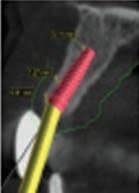

Due to the severity of intrusion, the treating dentist decided to perform surgical repositioning and stabilize with a physiologic splint. Local anesthesia was achieved with the use of 20% topical benzocaine gel and infiltration with 25 mg of 2% lidocaine with 1:100,000 epinephrine. Surgical repositioning of the maxillary left permanent central incisor was achieved with the use of gentle force with straight maxillary forceps (#99C). Figure 2 shows the position of the tooth after surgical repositioning.

A 0.016” Nitinol wire with bonded composite resin was used to secure the repositioned tooth. The physiologic splint engaged all the 4 maxillary permanent incisors. The radiograph in Figure 3 shows the repositioned tooth with splint in place. The patient was very anxious about feeling pain and about how much it would hurt. However, the pediatric dentist was able to use basic behavior guidance techniques such as tell-show-do, verbal reassurance and positive reinforcement to complete the treatment.

Figure 2. Position of the intruded tooth after surgical repositioning.

Figure 3. Radiograph of repositioned tooth with physiologic splint in place.